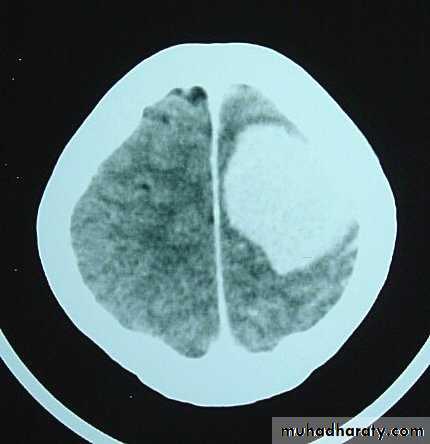

• Computed Tomography (CT-scan):

• Site and size of the tumour.

• Boundaries of the tumour.

• If there is surrounding oedema or not.

• Shift of the midline structures by the mass.

• Associated hydrocephalus.

• Bony changes.

• Nature of the tumour (solid, cystic, necrotic or calcified), and so its pathology.

Malignant GliomaPre contrast CT

Malignant Glioma Post contrast CT